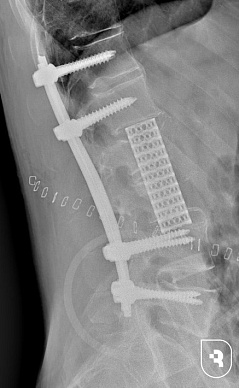

Специалисты НИИТОН СГМУ провели сложнейшую двухэтапную реконструкцию поясничного отдела позвоночника. Сначала пациенту установили полисегментарную транспедикулярную фиксацию позвоночника, обеспечив прочную стабилизацию костной ткани. Послеоперационный период прошел без осложнений. Затем, спустя месяц, была проведена обширная резекция тел пострадавших позвонков и установлен опорный металлоконструкционный имплант, позволивший восстановить целостность позвоночника и предотвратить возможные осложнения.

Результатом сложнейших операций стало полное устранение болей и значительное улучшение состояния пациента. Если до начала вмешательств боль измерялась на уровне 8 баллов по визуальной аналоговой шкале, то после полного курса реабилитации она полностью исчезла. Мужчина выписан на амбулаторное долечивание.